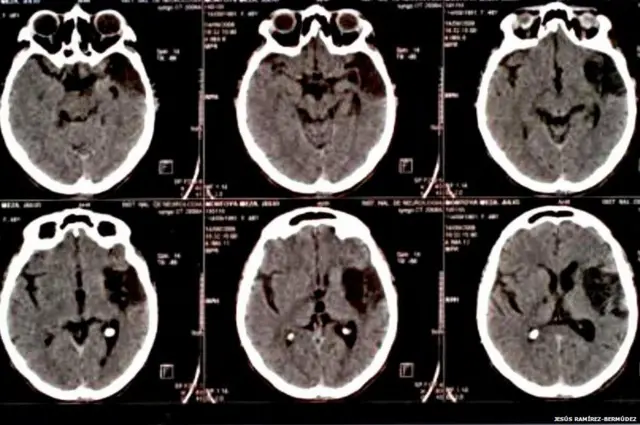

Kaynak, Jesus Bermudez-Ramirez

Meksika'da Nöroloji ve Nörocerrahi Ulusal Ensititüsü'nde çalışan Jesús Ramírez-Bermúdez'in liderliğinde hazırlanan 2010 tarihli araştırmada sendromun iki faktörün bileşiminden ortaya çıktığı belirtiliyor.

Nörolojik nedenler ise beynin içgözlem bölgesindeki düşük metabolik düzey, beyin küçülmesi ya da genişlemesi, düşünceleri, mantığı ve davranışları düzenleyen alnın arkasındaki beyinde hasar olarak gösteriliyor.